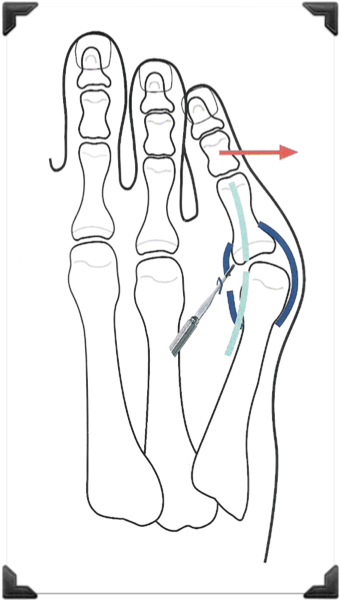

Principios de la Técnica

Corrección en el ápice o ángulo de la deformidad

Fijación Dinámica Blanda

- Osteotomías

- Tenotomías y Capsulotomías

- Realineación Anatómica

Dedo Supraducto - Metatarsalgia

Pre y Post op

Dedo Supraducto - Metatarsalgia

Pre y Post op